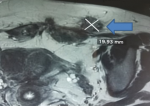

Figure 2: coupe coronale d´une IRM pelvienne en pondération T1 séquence saturation de graisse (fat sat); nodule paramédian gauche siégeant sur la cicatrice de césarienne mesurant 17x19 mm